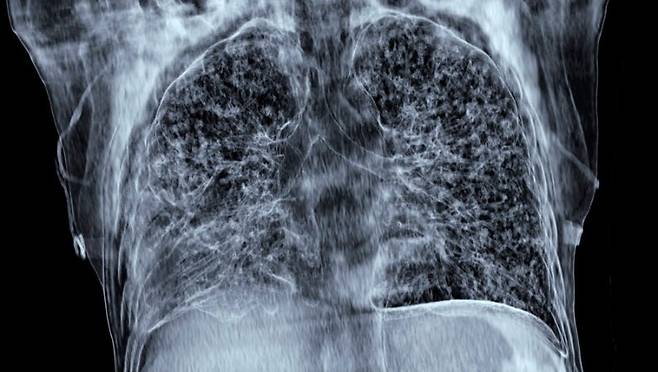

3. 영상 검사

• CT 스캔: 폐 농양의 크기, 위치, 주변 조직과의 관계를 상세히 평가할 수 있습니다. CT 스캔은 흉부 X선보다 더 정확한 정보를 제공하므로, 폐 농양이 의심될 경우 CT 스캔을 시행하는 것이 좋습니다.